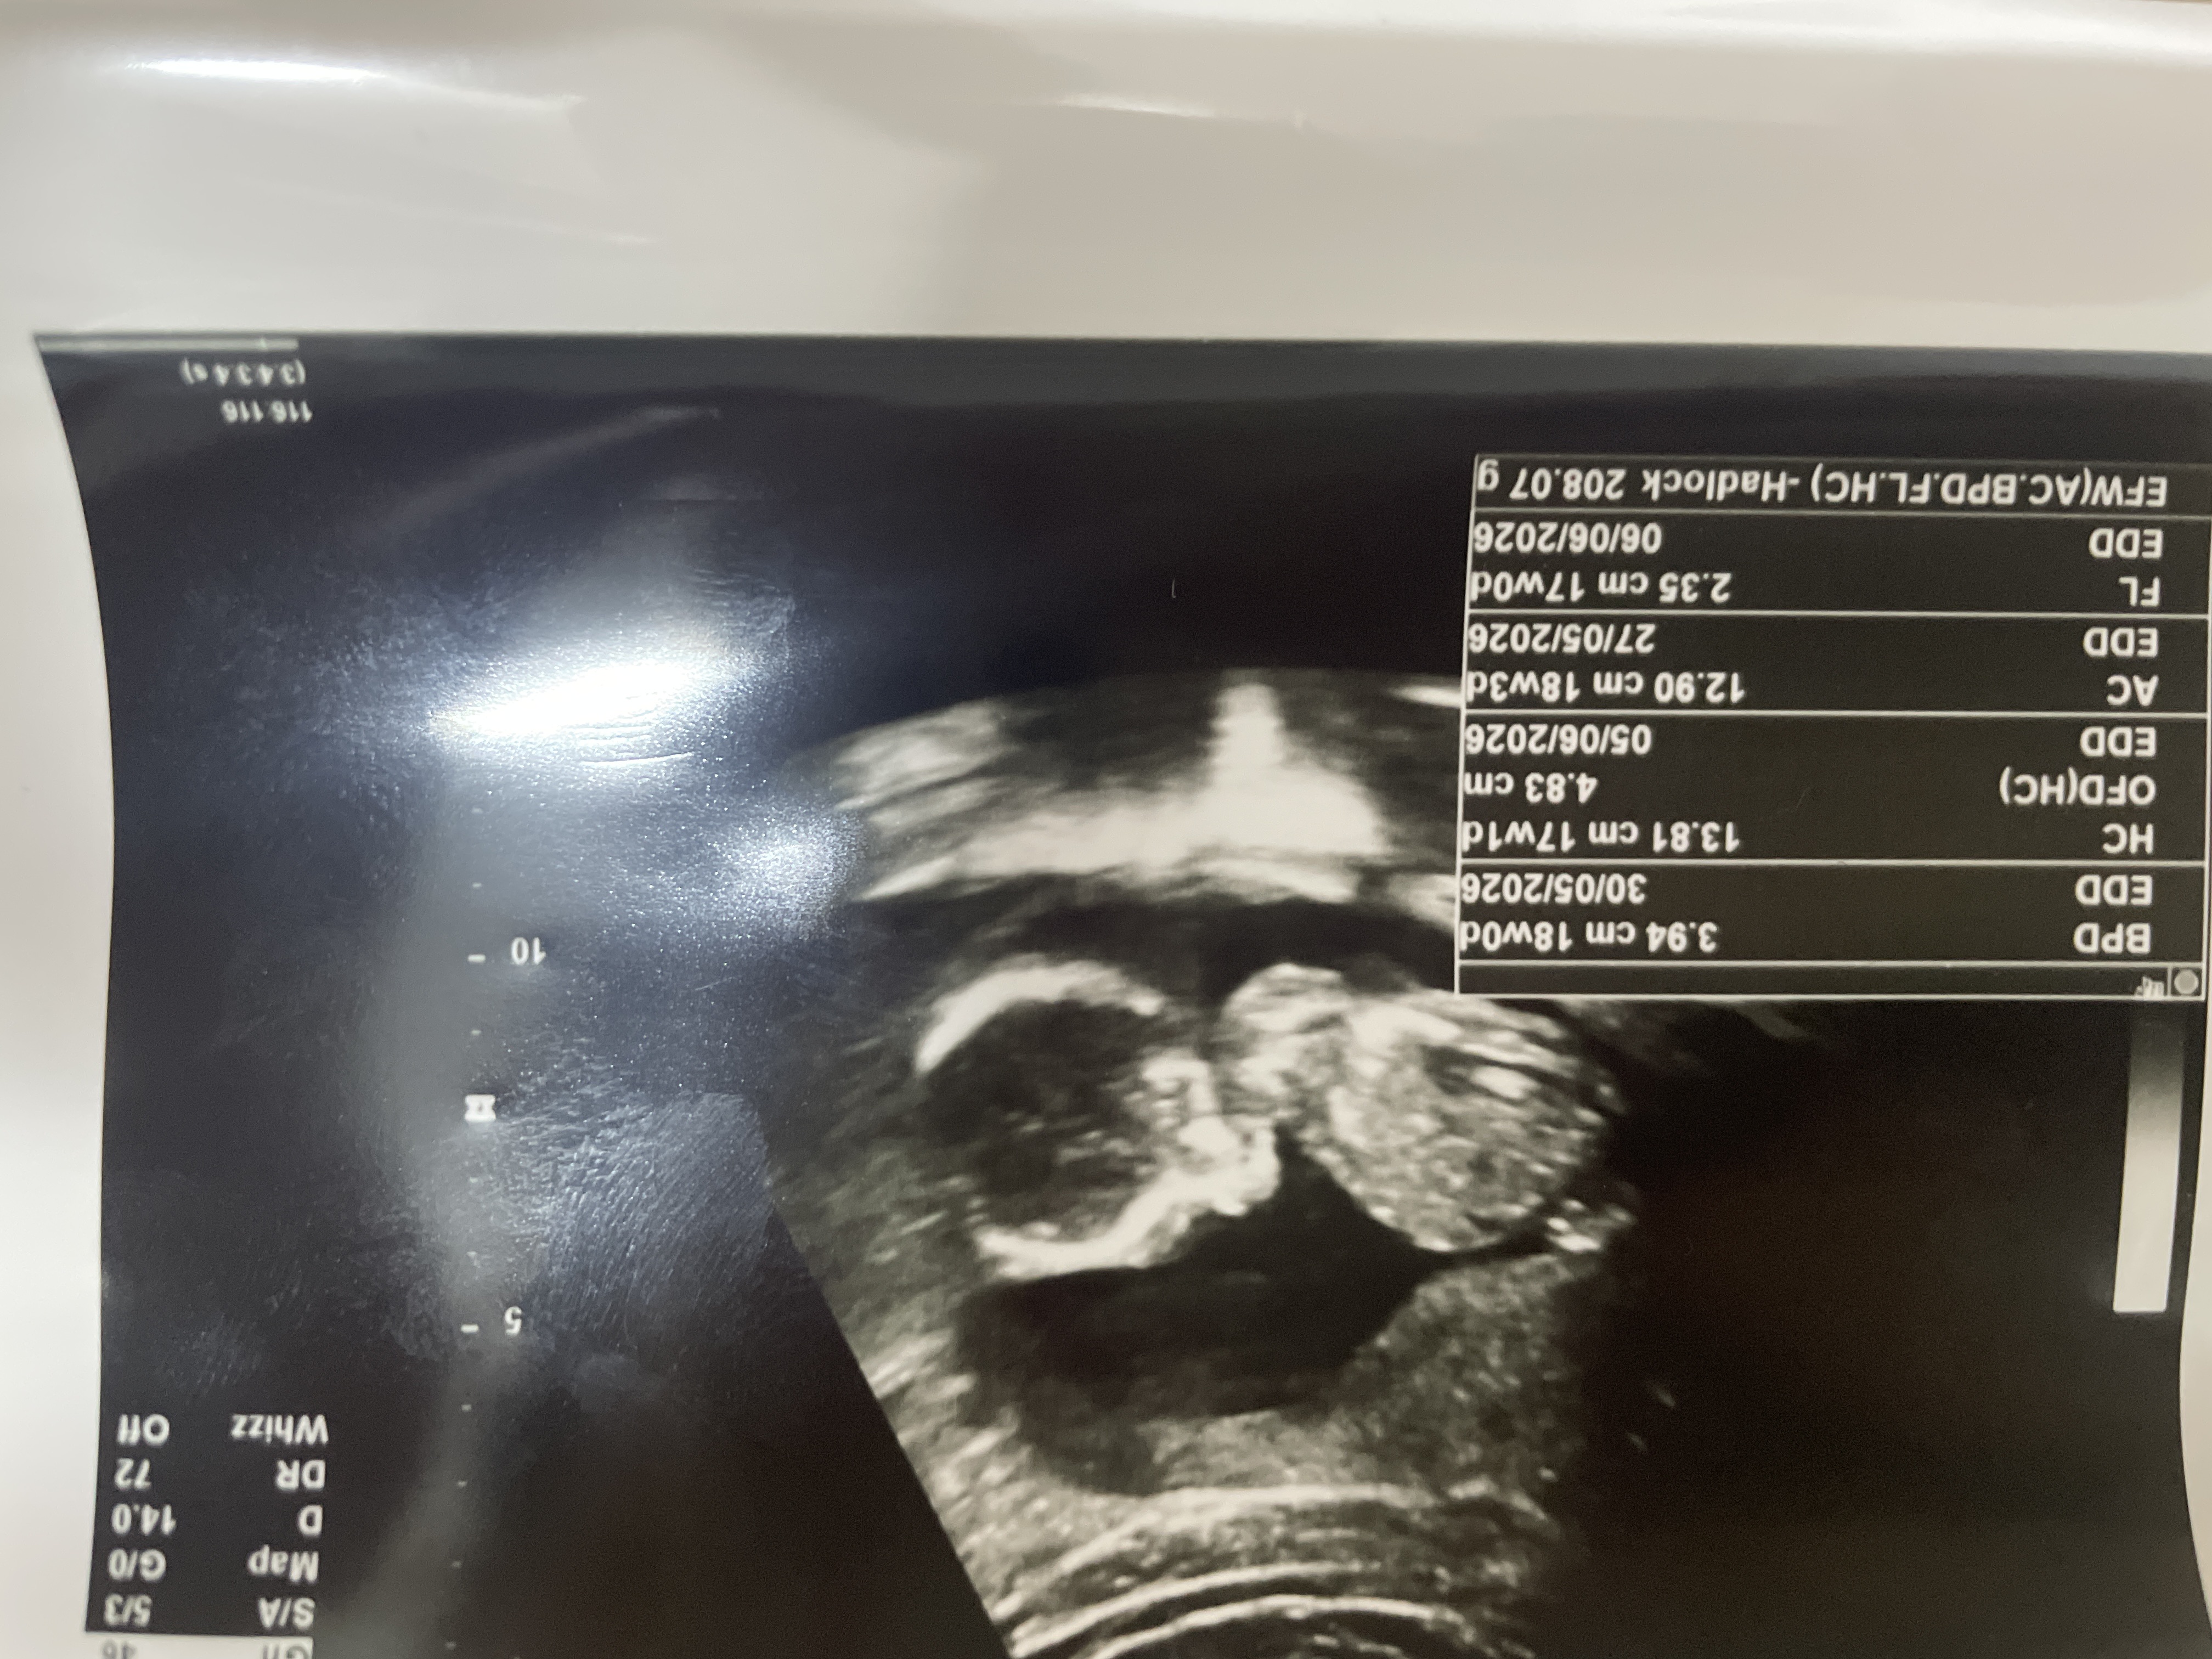

هل يمكن معرفة جنس الجنين في الأسبوع الـ17 من السونار ثلاثة اشهر ونصف

يمكن معرفته بالسونار ولكن ليس من الصورة المرفقة 0 2025-12-28T12:23:23+00:00

يمكن معرفته بالسونار ولكن ليس من الصورة المرفقة